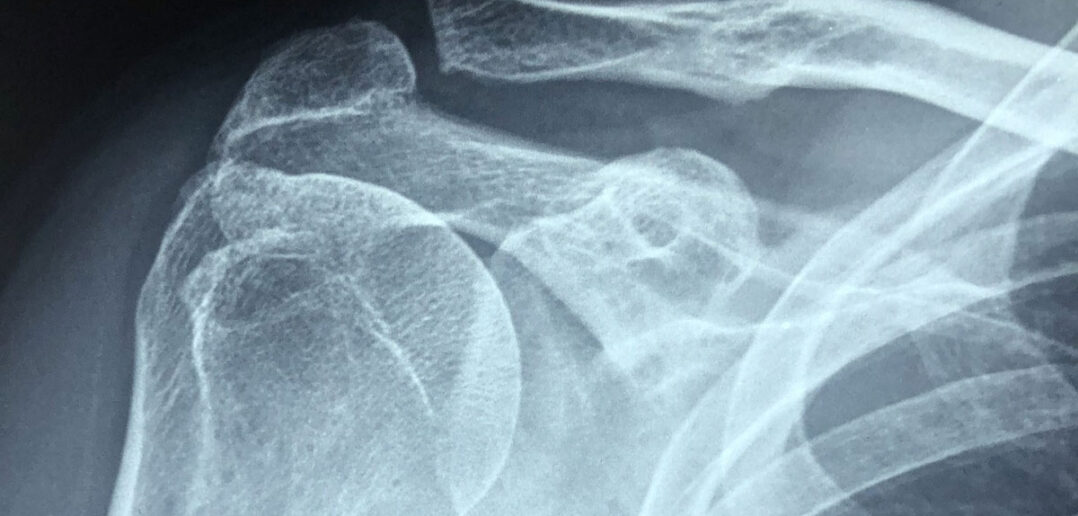

Dr. Bernhard Dickreiter: Durch eine Knochendichtemessung erkennt der Facharzt den Abbau des Knochengerüstes. Besteht der Verdacht auf eine solche Erkrankung, so lässt sich per Röntgenbild eine stark fortgeschrittene Osteoporose durch eine vermehrte Knochentransparenz im Vergleich zum gesunden Knochen feststellen. Sinnvoll ist zudem im Winter regelmäßig eine Kontrolle des Vitamin-D-Spiegels; dabei lässt sich eine Unterversorgung in dieser Jahreszeit recht einfach feststellen. Im Sommer liegen die Werte dagegen meist deutlich höher beziehungsweise im Normbereich.